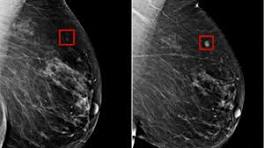

Watch: See how AI detected woman's breast cancer 4 years before it developed | CNN CNN's Poppy Harlow speaks with Dr. Larry Norton, the medical director of the Lauder Breast Center at the Memorial Sloan Kettering Cancer Center, ...